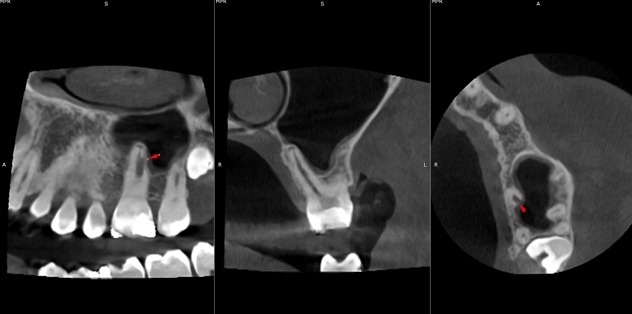

Surgical management of external cervical resorption lesion

Pre-op X-ray